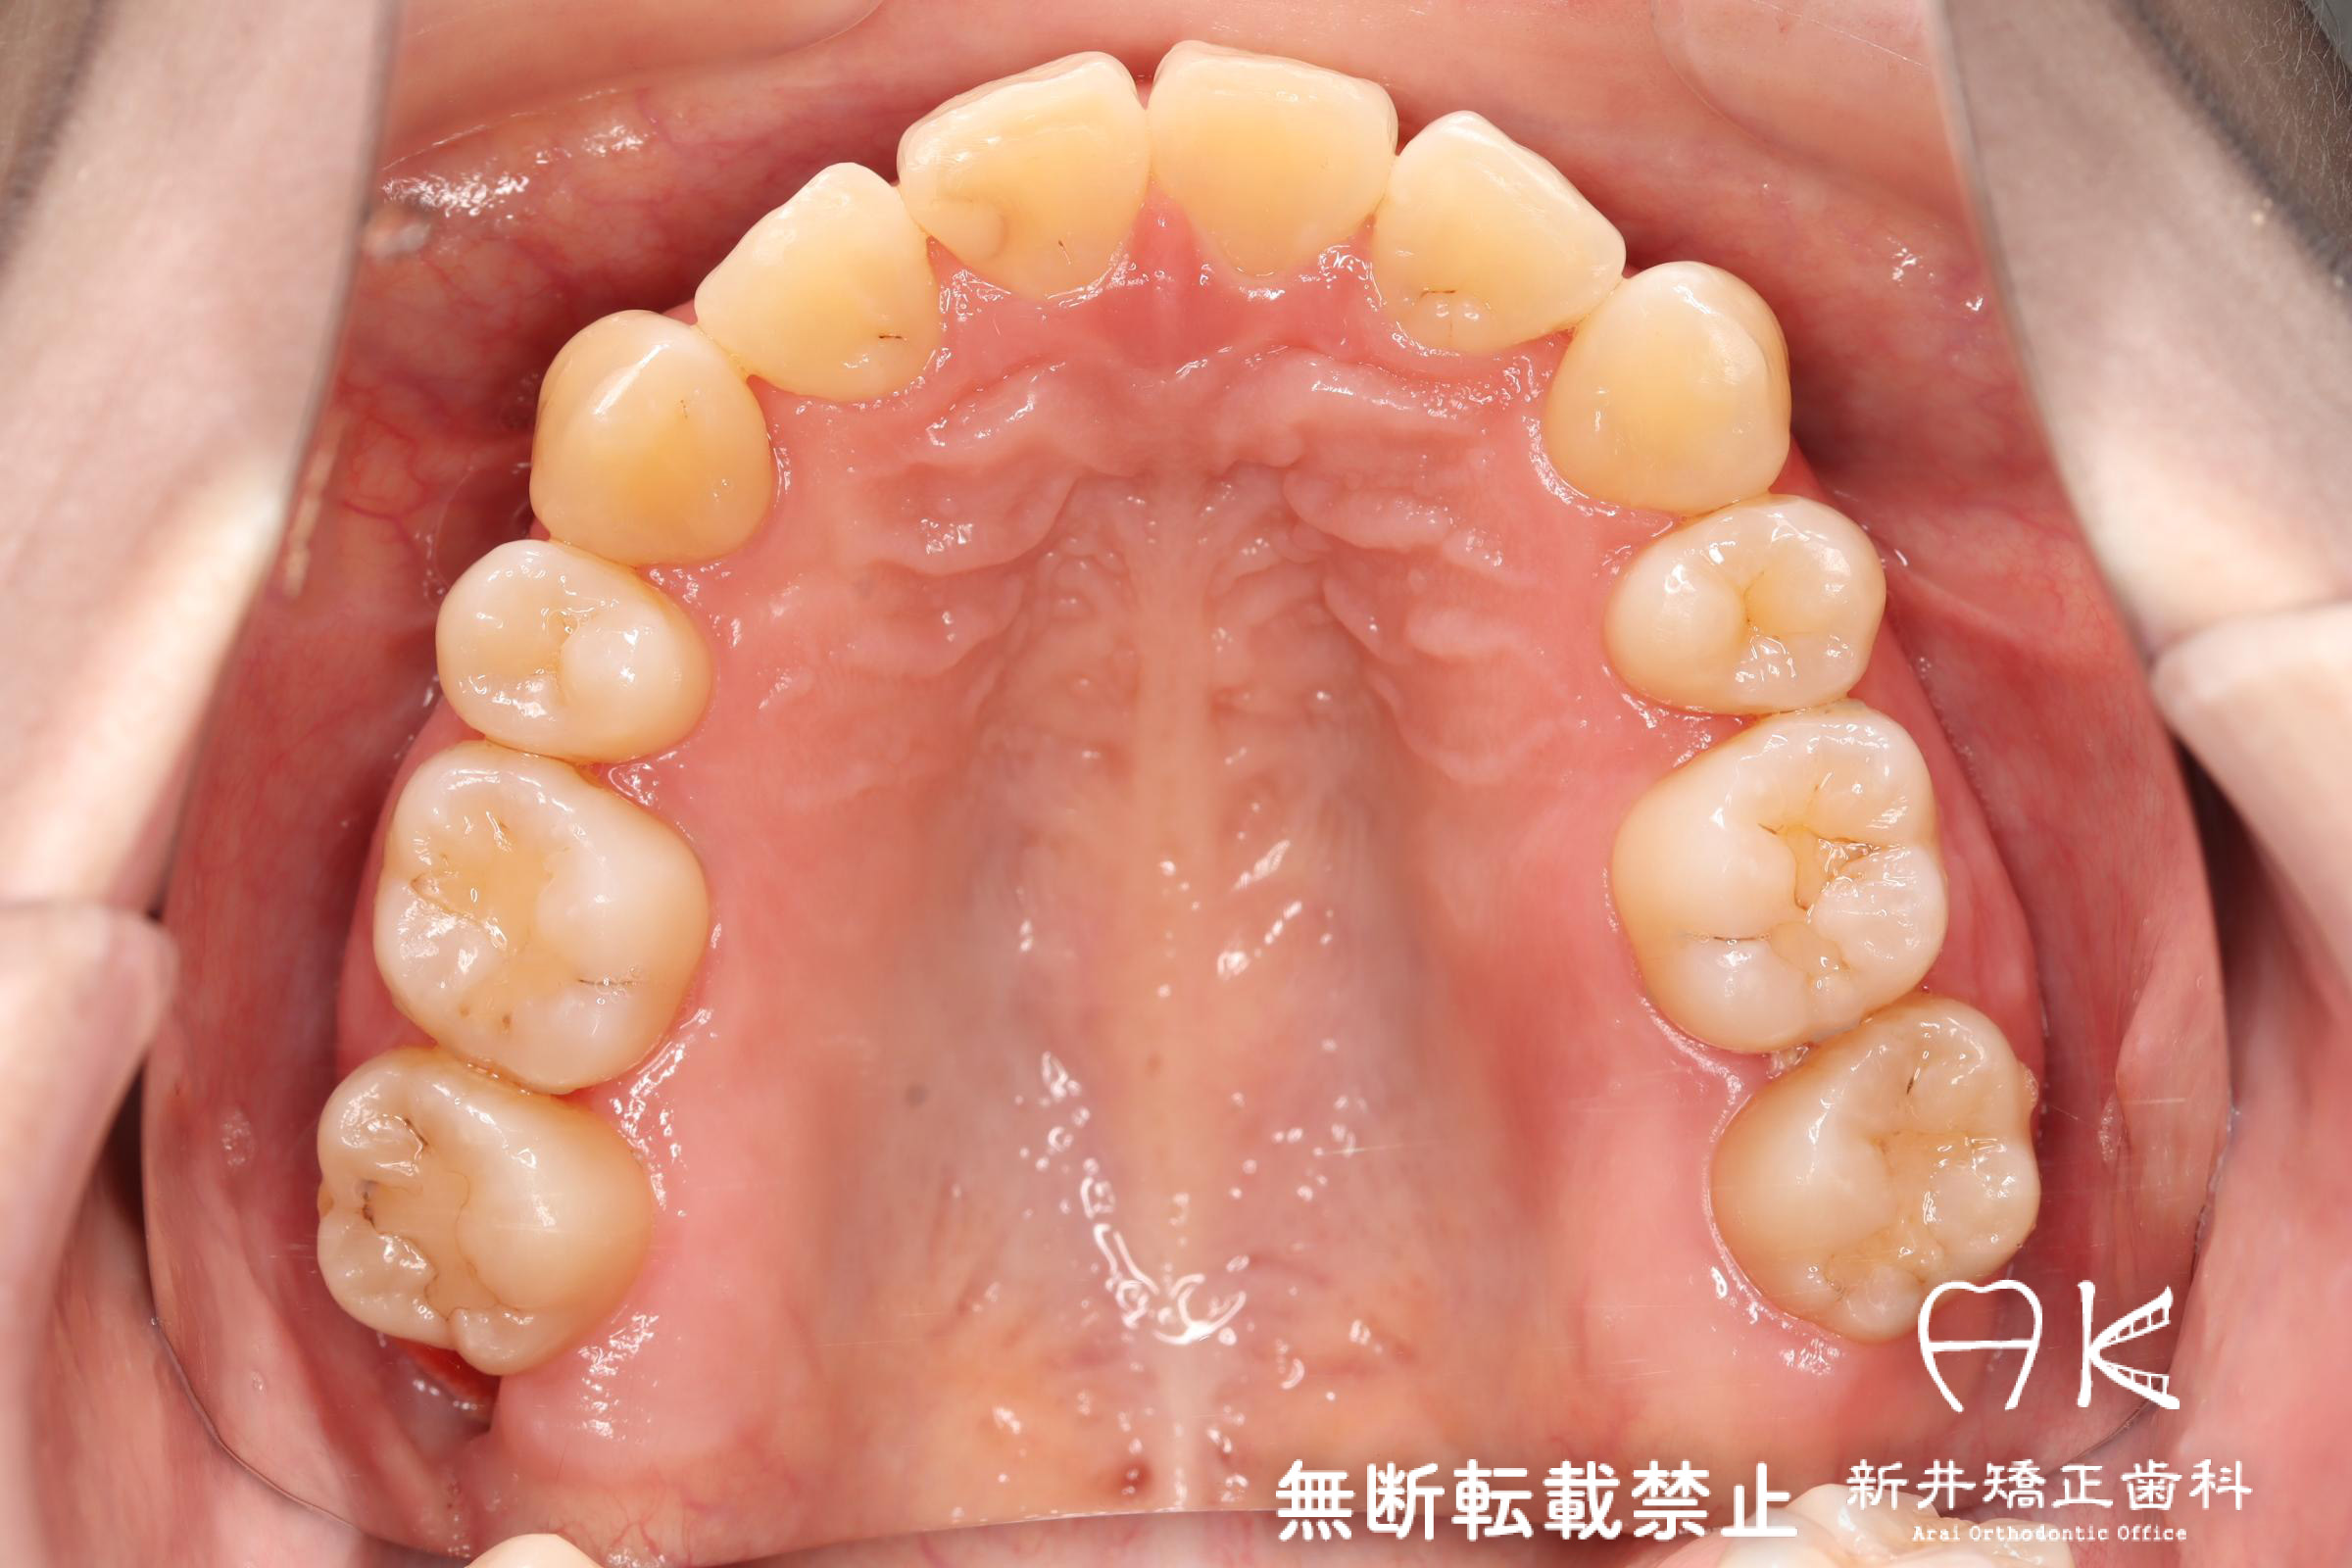

治療前後の解説

| 治療前 | 骨格的には受け口の患者さんですが、上顎前歯の唇側傾斜が大きく、患者さんとしては出っ歯だと思われていたパターンです。 元々口元の突出感はほとんどなかったため、歯を抜かずに上下顎ともに歯列を後方に移動させることにより主訴を改善させることとしました。 |